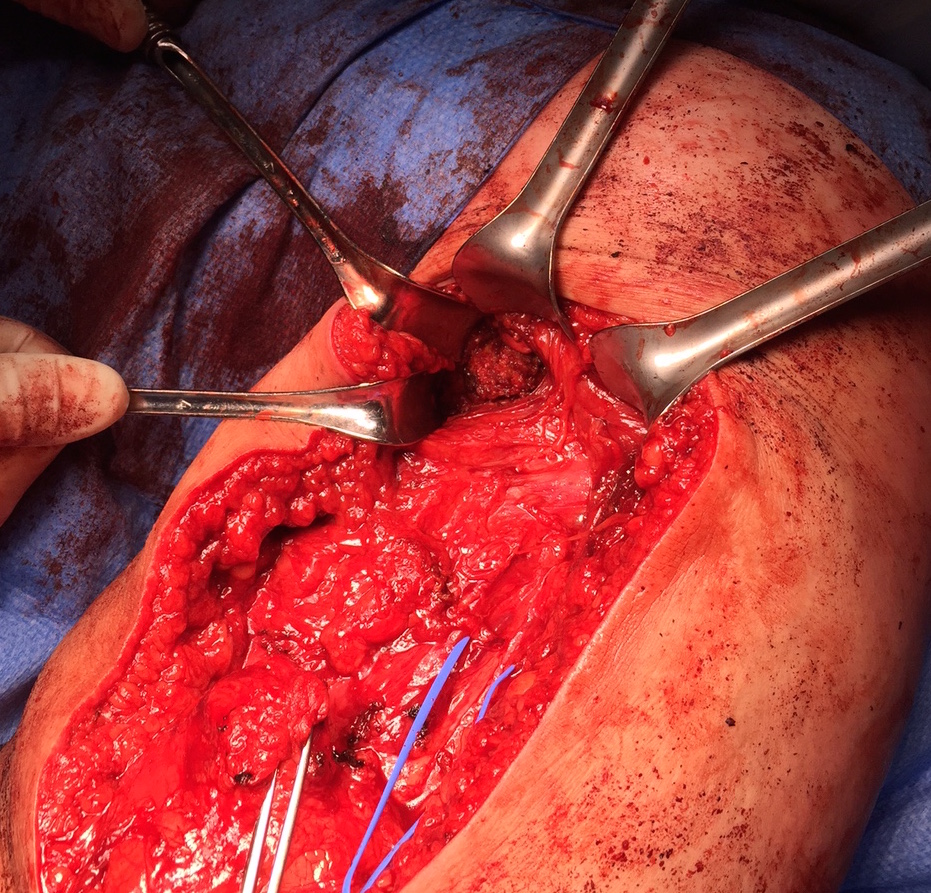

- 2 - 3 suture anchors, double loaded

Exposing ischial tuberosity (*) with Cobb retractor

Post suture anchor repair